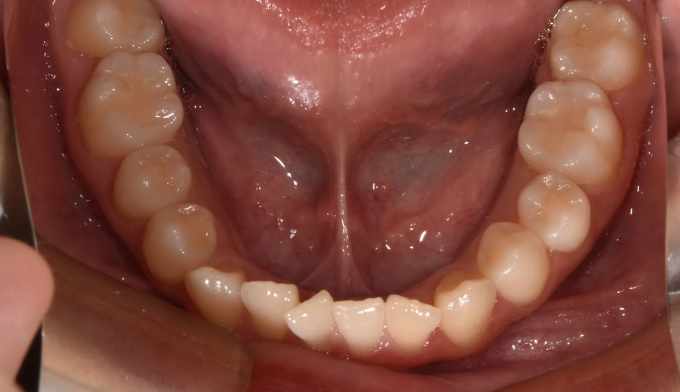

덧니

얇은 입술과 뒤로 들어간 입술을 가지고 있기 때문에 발치를 하지 않고 확장과 후방이동을 통해 최대한 공간을 마련하여 교정하기로 하였습니다.

덧니뿐만 아니라 앞니의 교합이 좋지 않아 윗니가 아랫니를 덮지 못하는 개방교합도 동시에 나타납니다.

총 교정기간은 21개월입니다.

원래 앞니의 길이가 위아래로 긴 형태를 가지고 있어서 치아의 길이를 조금 더 줄이면 보다 더 심미적이고 조화로운 형태를 나타냈을텐데, 환자가 치아의 형태를 바꾸길 원하지 않아 조금은 아쉬운 결과를 보입니다.